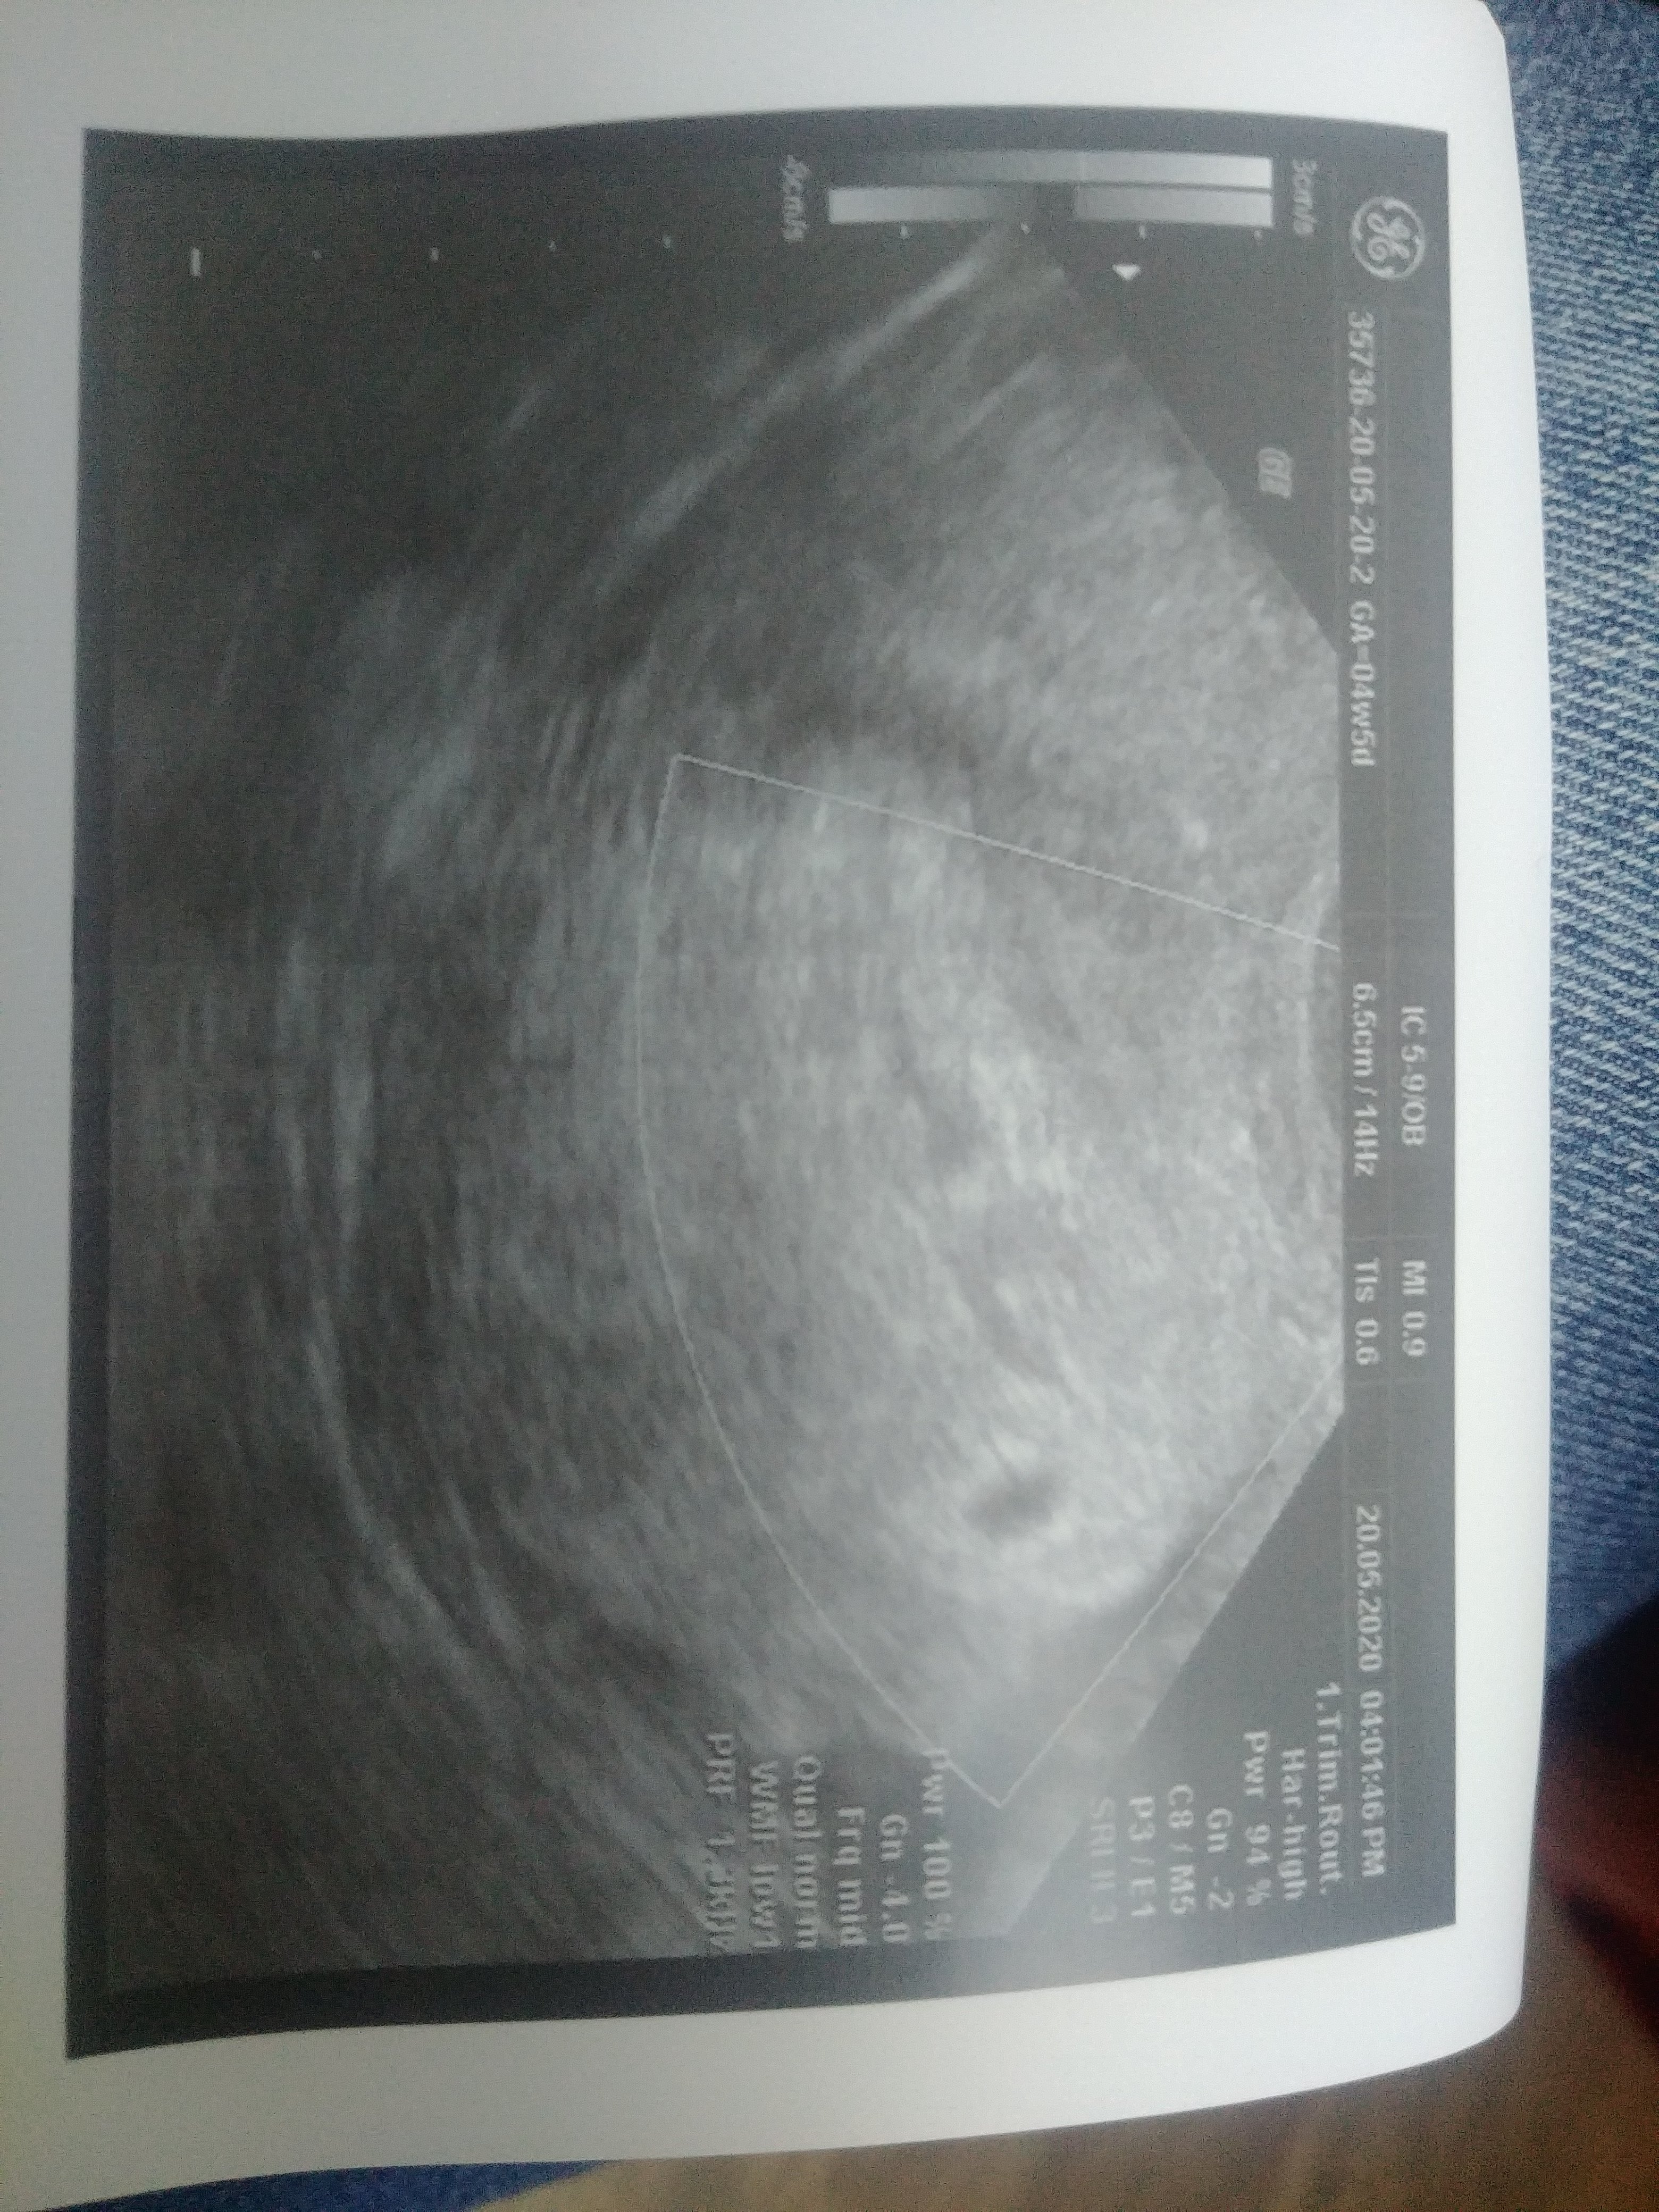

Moje 4 mm szczęścia ❤❤❤

Załączniki

• 20200520_175948.jpg

20200520_175948.jpg

2,3 MB · Wyświetleń: 116